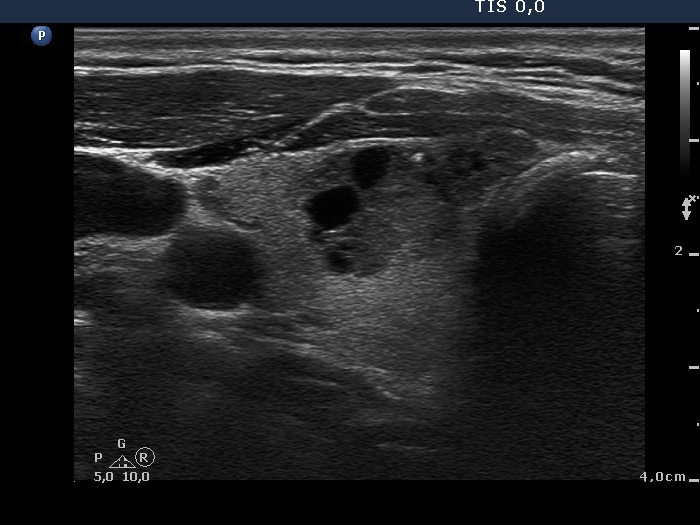

First examination (first and second rows of images)

Ultrasonography. The thyroid was echonormal. There were two moderately hypoechogenic nodules in the ventromedial part of the right lobe. One of them presented irregular borders, hyperechogenic granules and cystic degeneration. The left thyroid contained several nodules with different echo structures.

Cytology was performed from the nodule in the right lobe and resulted in benign, follicular proliferation..